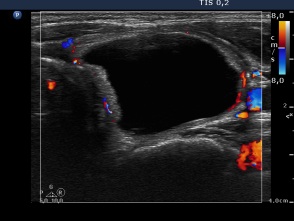

First session of sclerotherapy (second row of images):

Clinical presentation: the patient was treated by another endocrinologist after surgery. The patient was well and euthyroid on daily 87.5 microgram levo-tiroxine replacement therapy. She noticed a lump in her right thyroid for 3 months. She was advised to undergo repeated surgical procedure.

Palpation: unchanged.

Ultrasonography remained unchanged.

We could aspirate 2 ml thick, brown cystic fluid and injected 3 mL ethanol.